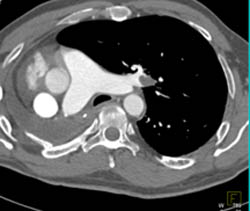

Subcarinal Nodes